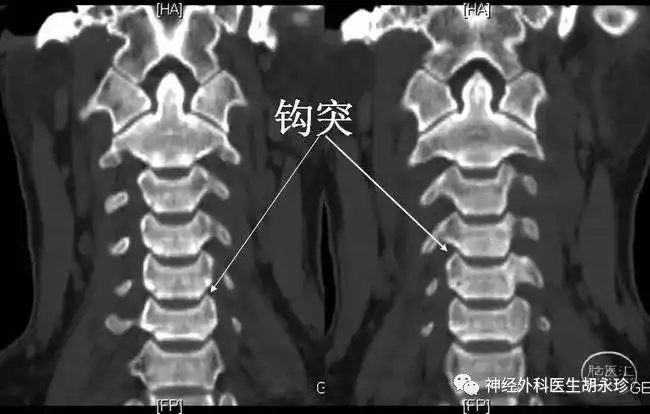

颈椎钩椎关节